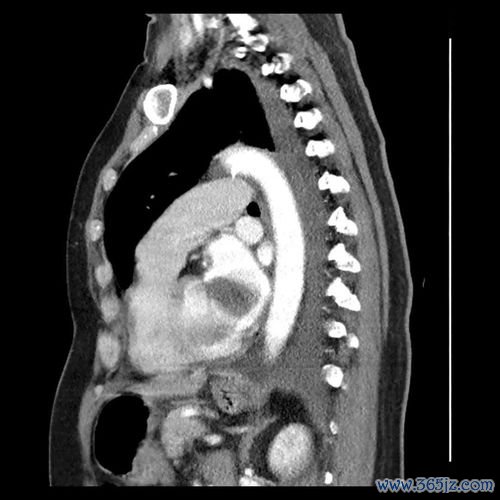

肝癌-乙肝携带者多年不复查,肚子胀发现肝癌破裂出血

引言:被忽视的“小毛病”与致命的转折 在快节奏的现代生活中,许多人都背负着健康“历史问题”前行,其中慢性乙型肝炎病毒(HBV)携带者是一个庞大的群体。对于部分携带者而言,由于早期可能没有明显症状,加之对疾病进展的轻视或对长期服药的顾虑,定期复查常常被置于次要位置,甚至被完全遗忘。肝脏是一个“沉默的器官”,当其内的隐患悄然滋长、最终爆发时,往往已酿成无法挽回的...